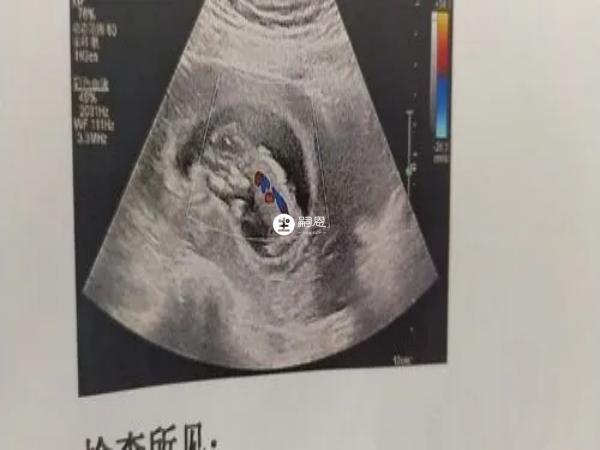

民間流傳著孕囊大小看男女的方法和技巧,如果B超檢查單上孕囊長和寬相等或相差無幾,表示懷女寶的可能性非常的大。

從孕期的B超影象進行觀察,如果孕早期孕胎囊形狀圓圓的,懷女寶的可能性比較大。